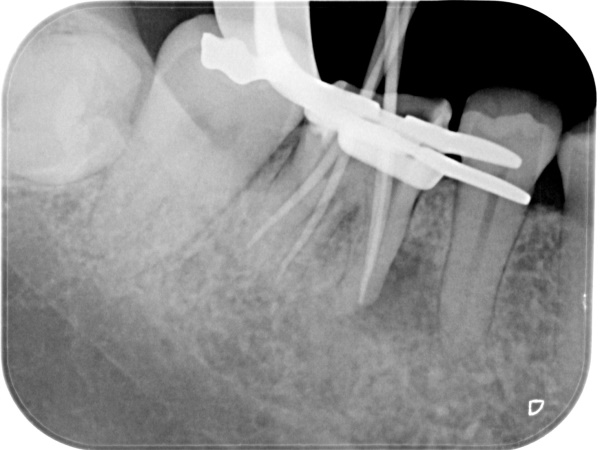

根管治療中(試適時)